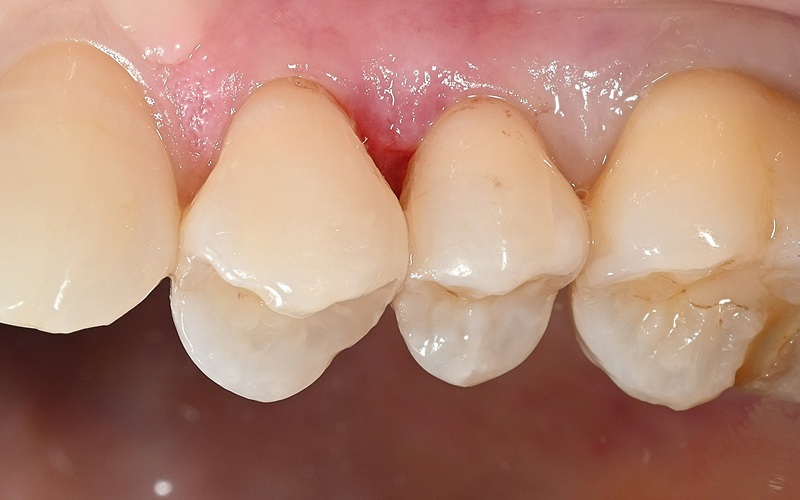

Case4

術前

術中

術後

| 治療名 | ダイレクトボンディング・セラミックインレー |

|---|---|

| 治療説明 | 以前他院で行ったハイブリッドセラミックインレーが劣化したためセラミックインレーとダイレクトボンディングで再修復を行いました。 |

| 治療回数・期間 | 2回 |

| 副作用とリスク | 一時的に知覚過敏が生じることがあります。セラミックとレジンが破折し、再修復が必要になる可能性があります。 |

| 料金(税込) | セラミックインレー:77,000円 ダイレクトボンディング:55,000円 合計:132,000円 |